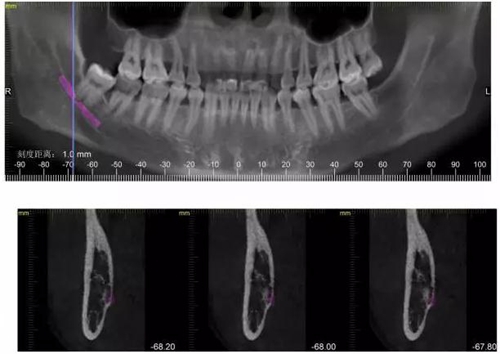

CBCT神經(jīng)管標(biāo)線,可以看到標(biāo)線不能連續(xù),中間被阻斷。